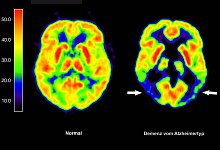

Gesundheit Antikörper Lecanemab: Wie er wirkt und wem er helfen kann Allein in Deutschland sind etwa eine Million Menschen von Alzheimer betroffen. Die europäische Arzneimittel-Behörde EMA hat für die EU nun erstmals...

Gesundheit Erste Alzheimer-Therapie in EU zur Zulassung empfohlen Die europäische Arzneimittel-Behörde EMA hat grünes Licht gegeben für die erste Alzheimer-Therapie in der EU, die auf die zugrunde liegenden...